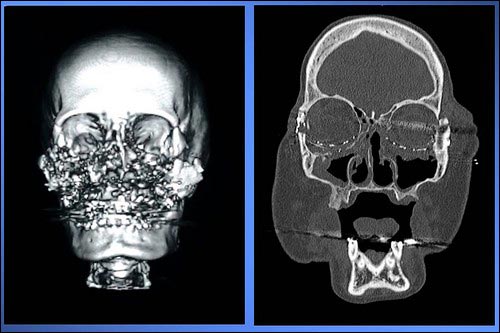

ومزقت رصاصة، في محاولة انتحارية قام بها الزوج عام 2004، وجه كوني كالب، 46 عاماً، تماماً وفقدت أنفها وخديها وفكها الأعلى. وتعرضت ملامح كالب للتشويه، كما فقدت القدرة على التذوق والشم والكلام جراء فقدان أنفها وشفتيها في الحادث، كما كانت تتنفس عبر فتحة جراحية في العنق.

وخلال الجراحة الماراثونية، أعاد فريق الجراحين تشكيل وجه الواهب ليتلائم والمريضة، وقاموا بوصل الأنسجة، والعظام، والأوعية الدموية والخلايا العصبية، وتركيب الأنف، والأجفان السفلية وأعلى الشفة، وملء الشواغر في وجه كالي.

قبل زراعة الوجه

بعد زراعة الوجه